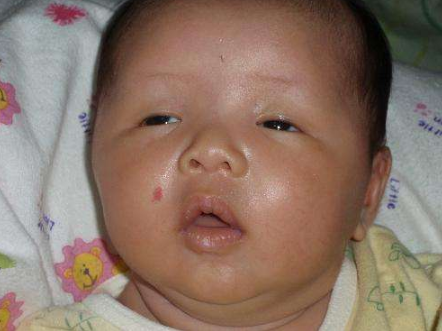

血管瘤圖片